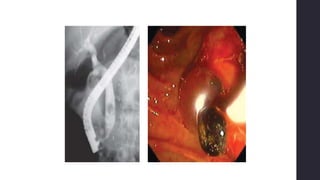

CPRE – GS (dx y

tx)• Enfinterectomía endoscópica + extracción del cálculo

⚫50% recurrencia (sin colecistectomía)

• Mortalidad <1%

• Complicaciones 5-10% (hemorragia, pancreatitis, conlangitis,

perforación retroduodenal)

*Cálculos de gran tamaño (>2cm), intrahepáticos, múltiples,

alteración de la anatomía gástrica o duodenal, cálculos impactados

y divertículos duodenales

endoscópicosCPRE + esfinterectomía endoscópica

o Éxito >90%

o Morbilidad: 5-9.8%

o Mortalidad: 0.3-

2.3%

Canastilla de Dormia

Las causas de falla de este

procedimiento incluyen:

a) Cálculo mayor de 1.5 cm de diámetro.

b) Dificultad para canular la vía biliar

c) Complicación temprana por la

esfinterotomía

d) Presencia de estenosis del conducto

hepatocolédoco con cálculo impactado.

e) Litiasis intrahepática.